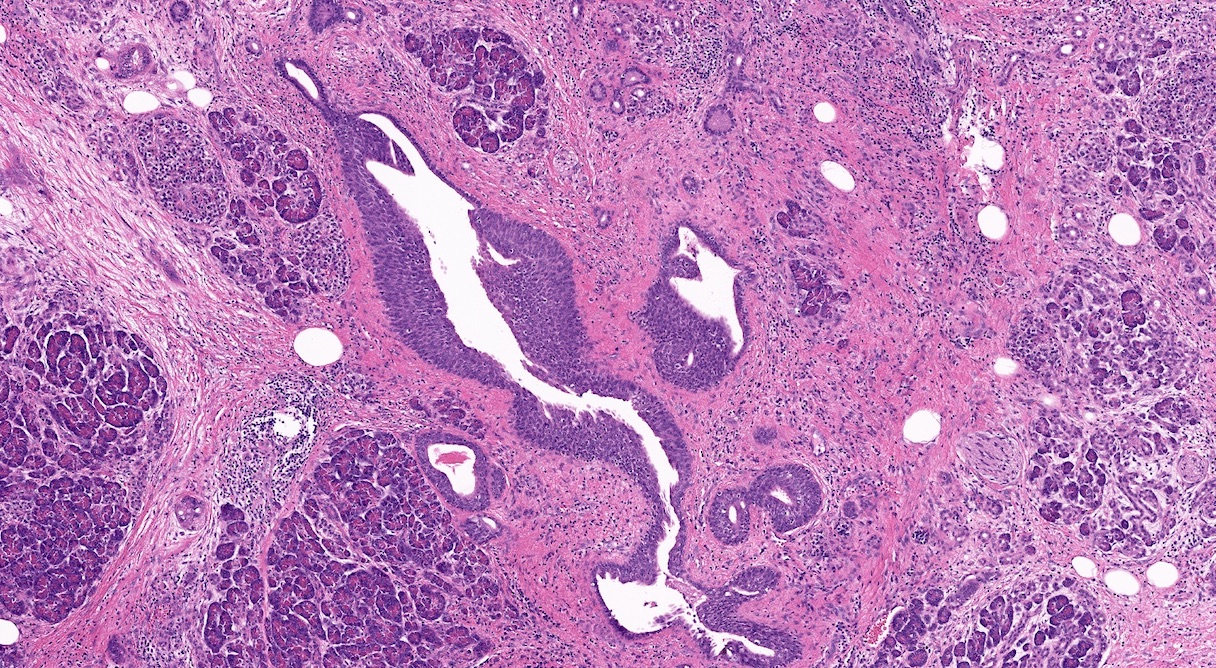

Microscopic (histologic) description

- Triad of cardinal features: fibrosis, loss of acinar tissue, duct changes (Pancreatology 2020;20:586)

- Ductal changes include distortion of ductal profiles, ectasia, presence of intraluminal concretions of amorphous material (so called protein plugs), squamous metaplasia, intraductal calcification

- Foci of low and high grade pancreatic intraepithelial neoplasia (PanIN) may be encountered

- Foci of periductal chronic inflammation and fat necrosis represent a common finding

- Paraduodenal pancreatitis shows Brunner gland hyperplasia, myofibroblastic proliferation in the duodenal wall, cysts lined by cuboidal ductal epithelium, which may be replaced by granulation tissue; multinucleated giant cells may be found (Cytopathology 2015;26:122)

Microscopic (histologic) images